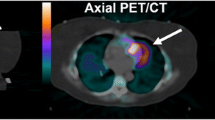

PET/CT, which provides anatomical and functional information, can be useful for tumor diagnosis, particularly regarding differential diagnosis, staging, response evaluation, and prognosis [1]. However, PET emission data acquisition is required for a few minutes per bed and also consists of several respiratory cycles. Therefore, the usual PET images are taken over an averaged state of respiration. The respiration-averaged PET images result in an underestimation of radioactivity and an overestimation of tumor volume in the thoracic and abdominal regions, especially in the vicinity of the diaphragm [2]. The underestimation of radioactivity increases the incidence of false-negative results. Some faint accumulations are not visible on images, and the standardized uptake values (SUV) of some lesions become low. Furthermore, the difference in temporal resolution results in a spatial misalignment between PET and CT data [3, 4].

To eliminate spatial misalignment between PET and CT images in motion objects, the averaging of CT images over respiratory phases has been proposed. Slow CT (SCT) is acquired with a long gantry rotation time that includes several respiratory cycles [5, 6]. Average CT (ACT) images were developed by averaging the CT images in all respiratory phases observed by four-dimensional CT (4DCT) acquisition in the cine mode [7]. These blurred CT images are reported to minimize misregistration between the CT attenuation correction (CTAC) and PET data acquired in static mode [6, 7]. Another method is gated acquisition to eliminate the effect of respiratory motion for PET emission data [8]. In the gated-acquisition protocol, PET emission data are continuously acquired in list mode as respiratory motion is monitored. The data are divided into several respiratory phases and are used to reconstruct PET/CT images of each respiratory phase. In addition, 4DCT was developed to better register CT and PET data acquired in gated mode [9]. 4DCT is acquired in cine mode using the respiratory system and is divided into phases similar to those of gated PET [10]. However, the effect of the combination of PET acquisition mode and CTAC has not yet been evaluated.